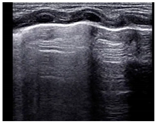

- The skin and underlying subcutaneous tissue.

- The thin layer of thoracic muscle.

- Ribs, which appear as oval-shaped or arch-shaped echogenic structures accompanied by anechoic vertical shadows. In the newborn, some ribs may not yet be calcified, especially in the anterior chest wall in preterm infants, and therefore no rib shadowing will be seen.

- Intercostal spaces framed by ribs and marked below by a thin, hyperechoic horizontal pleural line.